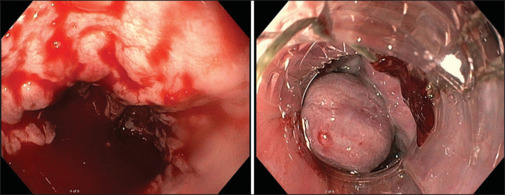

Sarcoidosis is a disease of unknown etiology, characterized by noncaseating granulomas. Generally, the condition primarily manifests in the lungs. Extrapulmonary involvement is common, but localization in the gastrointestinal system is rare. Here, we present the case of a 37-year-old male who became increasingly hemodynamically unstable during the diagnostic workup for sarcoidosis due to acute variceal bleeding. The underlying mechanism was later attributed to portal hypertension caused by hepatic involvement of the disease. This case demonstrates the importance of considering variceal hemorrhage as a rare but life-threatening complication of gastrointestinal localization of sarcoidosis.